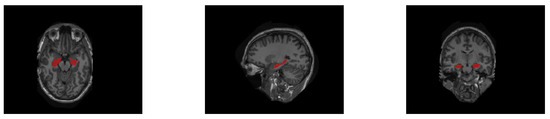

4.3. Implementation Details

The segmentation labels of the MICCAI dataset are multi-atlas, including 15 different labels, such as amygdala, caudate, hippocampus, etc. Howerver, in this work, only the labels of the hippocampus are useful. Thus, the segmentation labels of the hippocampus are first separated from the multi-atlas MRI images of the MICCAI. The processed MICCAI labels are displayed in Figure 8.

Figure 8. Three different dimensional slices of the hippocampus segmentation labels on the MICCAI dataset.